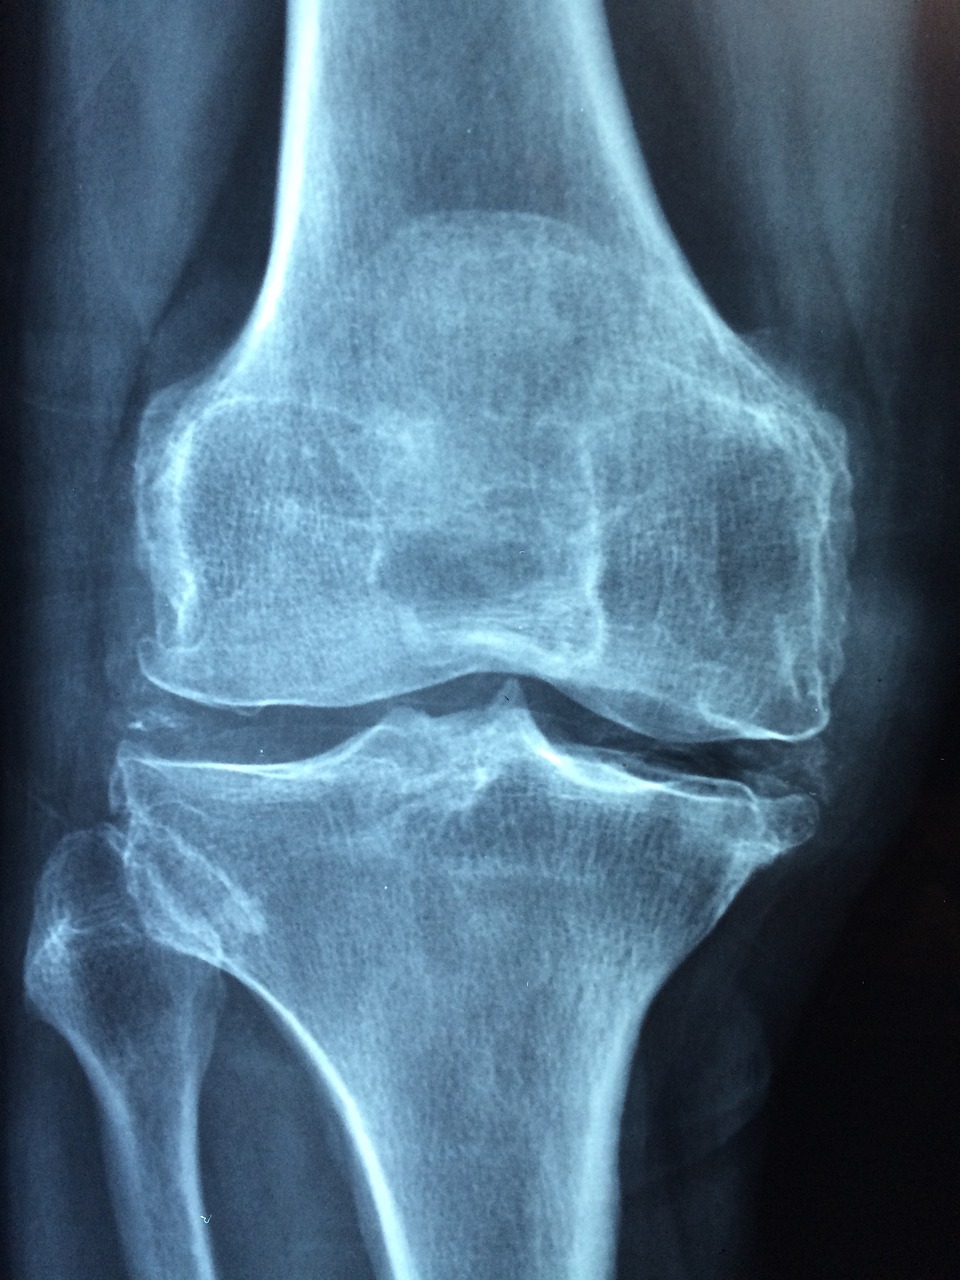

골다공증은 초기에 증상이 거의 없어 자각하기 어려운 질환입니다. 따라서 정기적인 골밀도 검사를 통해 뼈 밀도를 점검하는 것이 중요합니다. 50세 이상의 여성이나 60세 이상의 남성은 정기적인 검사를 받는 것이 좋습니다. 조기 발견하면 골절 위험을 줄일 수 있습니다.